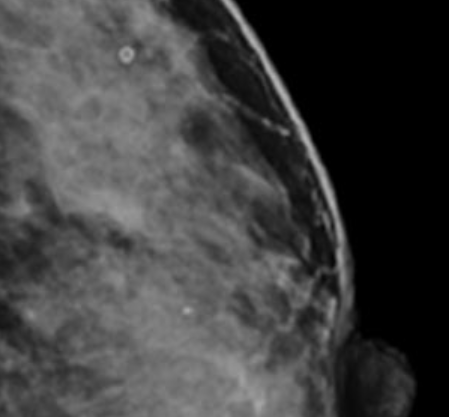

유방 미세석회화는 유방 조직 내에 칼슘 성분이 미세하게 침착된 현상을 말합니다. 이러한 석회화는 보통 크기가 매우 작아 육안으로는 확인이 불가능하며, 유방촬영술(mammography)을 통해서만 발견됩니다. 미세석회화는 대부분 증상이 없어 건강검진이나 유방촬영에서 우연히 발견되는 경우가 많습니다.

미세석회화는 유방 내 다양한 원인으로 발생할 수 있습니다. 양성 질환인 섬유낭종, 유방 낭종, 유선증, 유방염 등에서도 나타날 수 있으며, 유방암의 초기 징후로도 나타날 수 있어 조기 진단에 중요한 역할을 합니다. 특히 유방암 중에서도 비침윤성 유관암(DCIS)의 약 90%에서 미세석회화가 관찰되기 때문에 유방암 조기 발견의 중요한 단서가 됩니다.